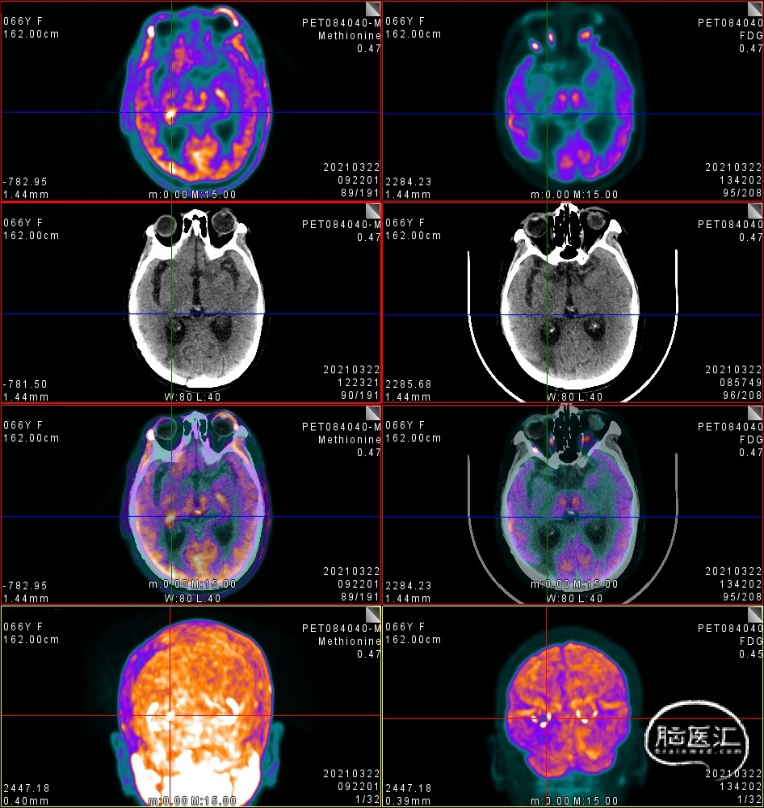

3. 2021年3月18日,2021年3月起,患者诉左侧肢体乏力,需搀扶行走。影像学检查显示,右侧脑室后角旁见结节样环形强化灶,直径7-8mm。MRS:NAA峰可见下降,Cho峰升高。Cho/Cr为0.748,Cho/NAA为2.13,考虑肿瘤复发可能。患者行射波刀治疗(24Gy/4FX),TMZ+安罗替尼2周期,TTFields重新定位,电场治疗调整贴片位置。